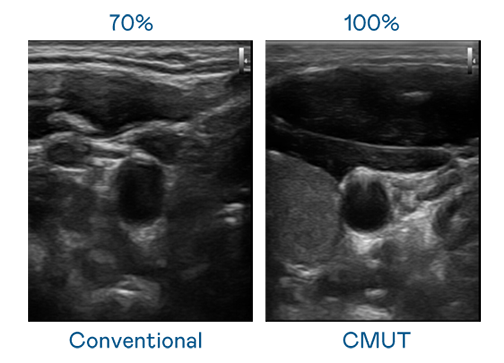

CMUT 技术是一种用电容式微机电元件来产生超音波讯号的技术。与传统 PZT 压电式技术相比,CMUT 频宽增加 30%,更宽频的超音波讯号让影像解析度大幅提升,是实现高影像品质医疗超音波扫描、促进精准医疗发展的关键技术。

大频宽带来超清晰影像

超音波影像的解析度高低,首先取决于探头能发出的讯号频宽。腾龙集团 CMUT 可提供高清晰的超音波讯号,提供高频宽、高灵敏度、影像纹理细节更高的超音波影像,协助医护人员缩短影像判读时间及利用精准的医疗影像进行诊断。